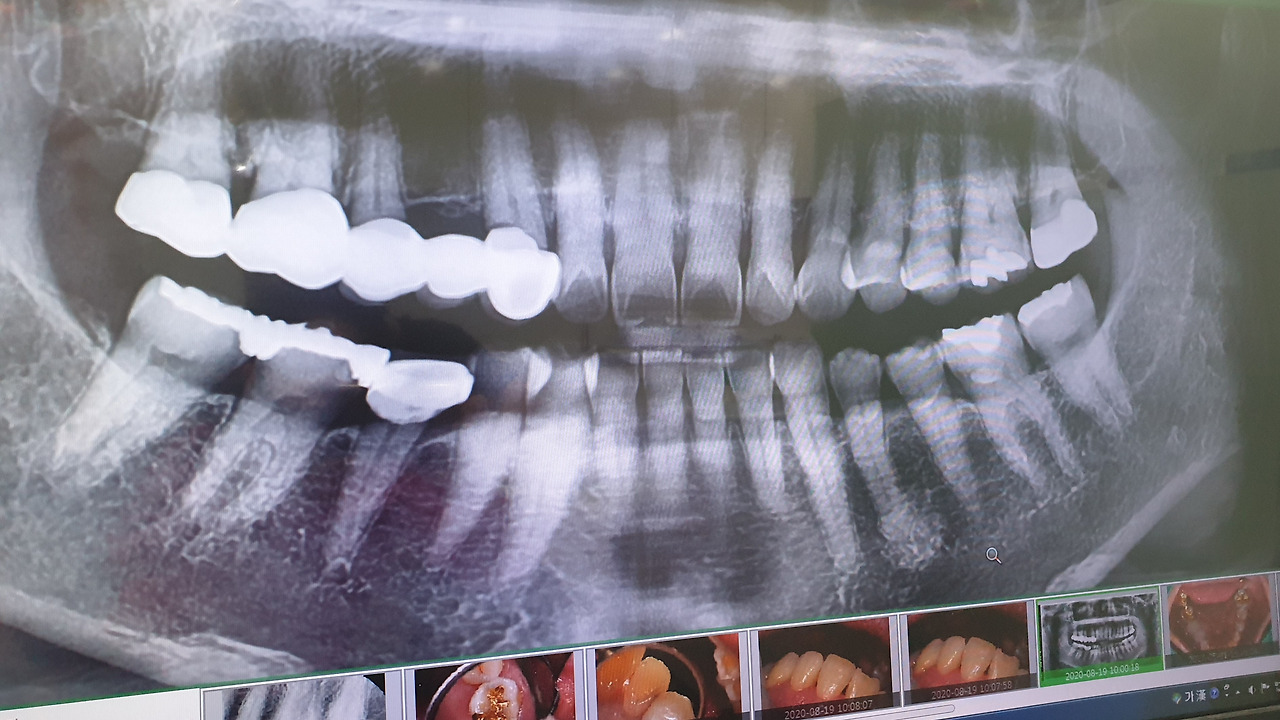

치아 X-ray

지난주에 자주 가는 치과에 예약을 하고 다녀왔다. 지난번 건강 검진할 때 치과 진료도 받았었는데 아무 이상이 없었다. 이번에는 그냥 6개월마다 가는 정기 검진이라고 생각하고 가벼운 마음으로 치과에 들어섰다. 치과 상호가 바뀌었다. 지난번 치과 원장님은 젊은 남자분이셨는데 정말 친절하고 편하게 치료를 잘해주셔서 우리 가족은 모두 이 치과를 이용하고 있다. 이번에는 여자 선생님이셨다. 치아를 살피시던 선생님께서 왼쪽 위 어금니 하나에 충치가 생긴 것 같다고 한다. 때운 금이 오래되어 살짝 들떠서 그 사이로 충치가 생긴 것 같다고 하셨다. 특별히 이가 시리거나 아프지 않아서 몰랐다. 이번 원장님도 꼼꼼하신 것 같아 마음이 놓였다.